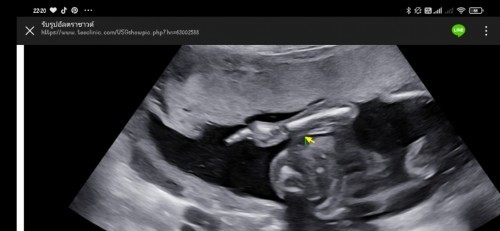

ตุลาค่ะแม่ ภาพนี้ตอน 23 weeks ปิดทุกอย่างให้เห็นแต่แขน หน้าไม่เคยได้เห็นเลยค่ะ ซาวด์มา3 ครั้ง หมอบอกลูกไม่รัก 5555555

ตอนนี้ 23w5d คุณหมอบอกผญ แต่อิแม่ดูไม่ออกค่ะ 😂